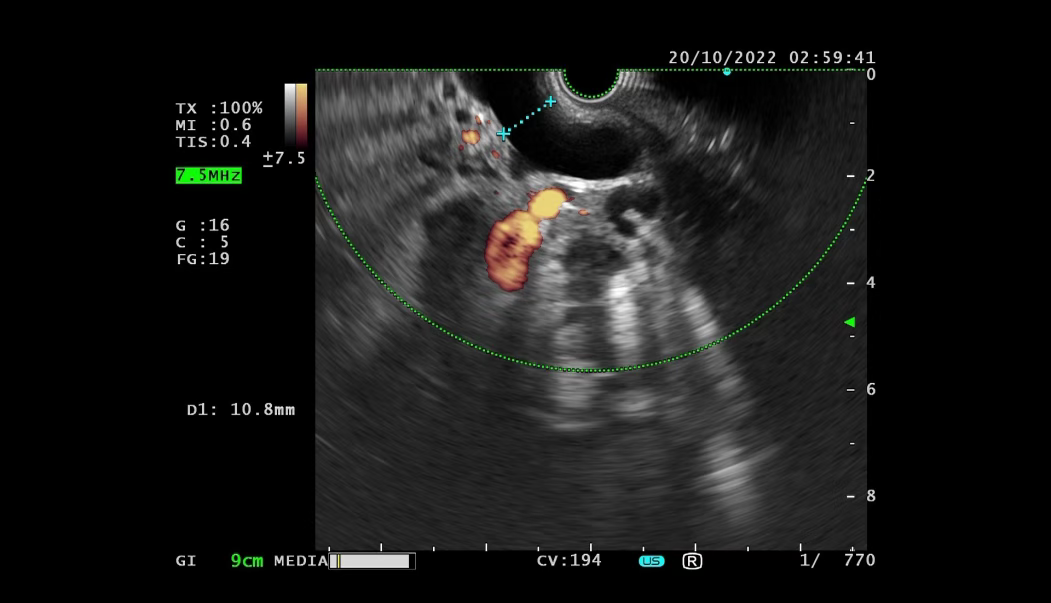

After admission, symptomatic treatments such as anti-infection therapy, enzyme inhibition, and fluid replacement were administered. Endoscopic retrograde cholangiopancreatography (ERCP) with nasobiliary drainage was performed. Endoscopic ultrasound revealed an irregular hypoechoic lesion in the pancreatic head, dilation of the main pancreatic duct, invasion of the pancreatic segment of the common bile duct, and a solid irregular lesion within the duct wall. An enlarged hypoechoic lymph node was observed near the portal vein. Pathological examination of the endoscopic ultrasound-guided pancreatic biopsy showed: (Pancreatic head puncture tissue) blood clot-like material with a small amount of pancreatic tissue, consistent with acute pancreatitis and necrotic changes.

Although the initial biopsy did not support a tumor diagnosis, abdominal MRI and endoscopic ultrasound suggested possible invasion of the common bile duct and enlarged lymph nodes near the portal vein. To avoid misdiagnosis, Spyglass examination was performed. Spyglass choledochoscopy revealed destruction, hyperplasia, and diffuse stenosis in the middle and lower segments of the bile duct, with fragile tissue prone to bleeding. Pathological examination confirmed adenocarcinoma of the distal common bile duct.